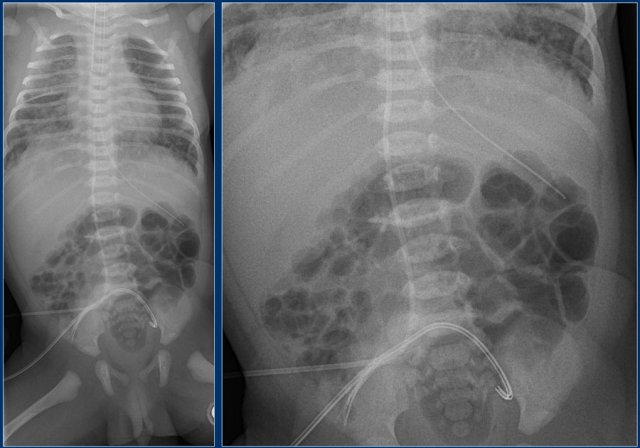

Umbilical artery line (3)

First study the images.

Then continue reading.

The findings are:

1. Malposition of umbilical artery line, folded in the abdominal aorta.